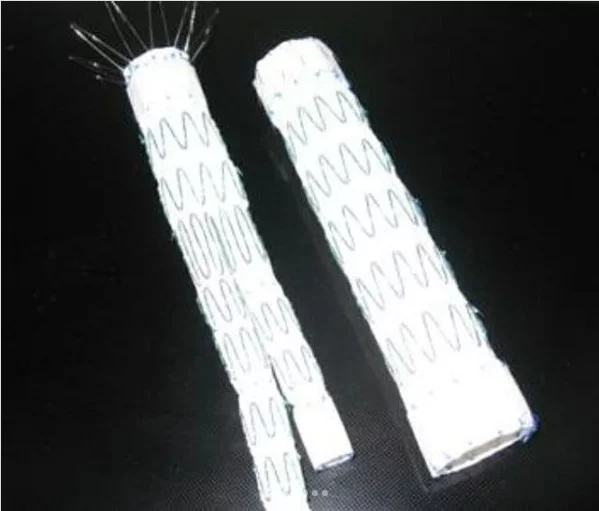

این بیماران با احساس ضربانات مداوم در شکم و درد و گاهاً بدون علامت در معرض خطر پارگی رگ اصلی بدن به نام آئورت ومرگ ناگهانی هستند .دیروز در کمتر از یکساعت بدون جراحی ، استنت هایی که پوشش دیواره ای دارند را مثل لوله داخل ناحیه آنوریسم/یا گشاد شده، تعبیه کردیم و آئورت به سایز نرمال برگشت.